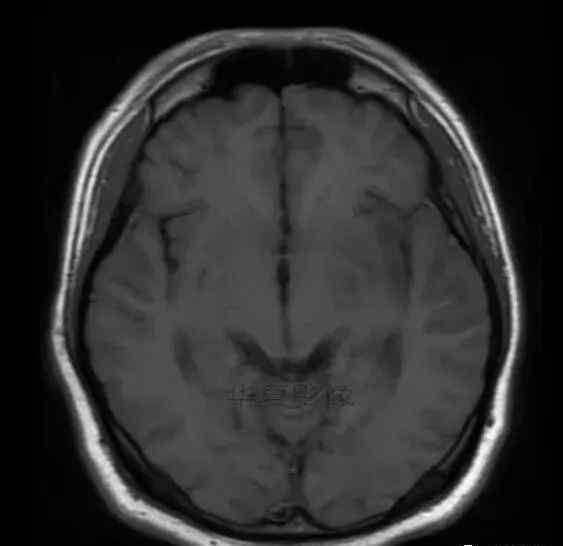

男,25岁,6天前意外感冒,现在发烧。他的体温超过39.0℃,他的呕吐物不是喷射状的。他的呕吐物是胃里的东西。

1.左侧颞叶、海马和岛叶T1WI信号低,T2WI信号高

2.病变没有明显的边界

3.占用效果不明显

4.豆状核不受影响